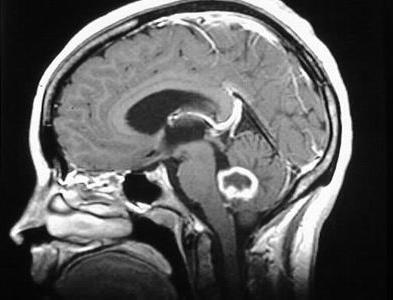

Процедуры визуализации. Магнитно-резонансная томография (МРТ) обычно применяется для постановки диагноза при опухолях головного мозга. Во время МРТ используются магнитные поля и радиоволны, которые генерируют изображение головного мозга. В некоторых случаях в вену руки вводится контрастное вещество до начала проведения МРТ. Несколько специальных изображений МРТ могут помочь врачу оценить ситуацию и назначить план лечения, включая проведение функциональной МРТ, перфузионной МРТ и магнитно-резонансной спектроскопии.